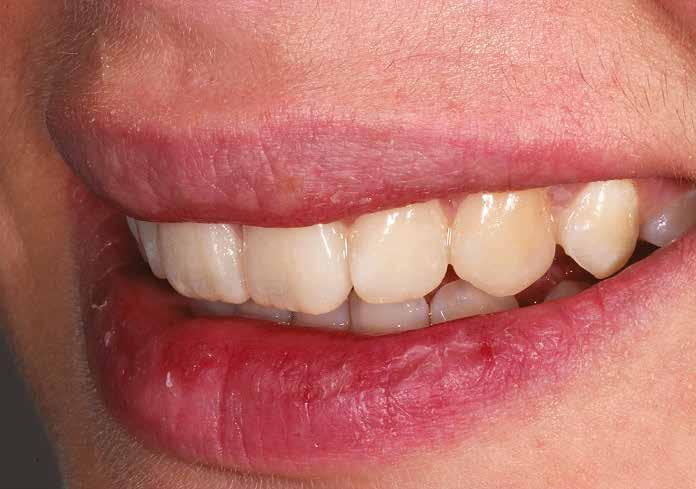

Hölgy páciensem az első konzultáció során tipikus kórtörténetet vázolt fel: Gyermekkora óta szeretett volna fogszabályozó készüléket, hiszen mindig is zavarta a class 2-es eltérésnél tipikusan jellemző nagy overjet (1-3. képek), és természetesen az ezáltal kifelé álló felső metszőfogai, részben a felső metszők protrúziója, részben pedig a disztálisan elhelyezkedő mandibula miatt. Annak ellenére, hogy több fogszabályozó szakorvosnál is járt az évek során, de mivel saggitális eltérése és az alsó metszőfogak torlódása miatt négy kisőrlőfog extrakcióját, illetve emellett sokszor állcsont műtétet is javasoltak neki, nem vágott bele a kezelésbe (4-5. képek).

A konzultáció során arról is beszéltünk – ahogy az ilyenkor lenni szokott –, sohasem szeretett igazán mosolyogni, de a Pitts Protokolloknak köszönhetően az arc- és mosolyesztétikai céloknak megfelelően kerül megvalósításra az okklúziós korrekció. Az okklúziós kezelési célok az alábbiak voltak: a felső és alsó fogív nivellálása és tágítása, az alsó fogsor/ mandibula mezializálása, valamint a harapás megemelése által a mélyharapás rendezése.

A fogkontúrálás és az interproximális redukció alkalmazásával a mikroesztétikai részletek tökéletesítése is megtörtént (11. kép) A kezelés mindössze 16 hónapig tartott, megtörtént a rágófunkció helyreállítása, és az esztétikai végeredmény sokéves várakozás után valóban fordulópontot jelentett páciensünk életében (12-14. képek).